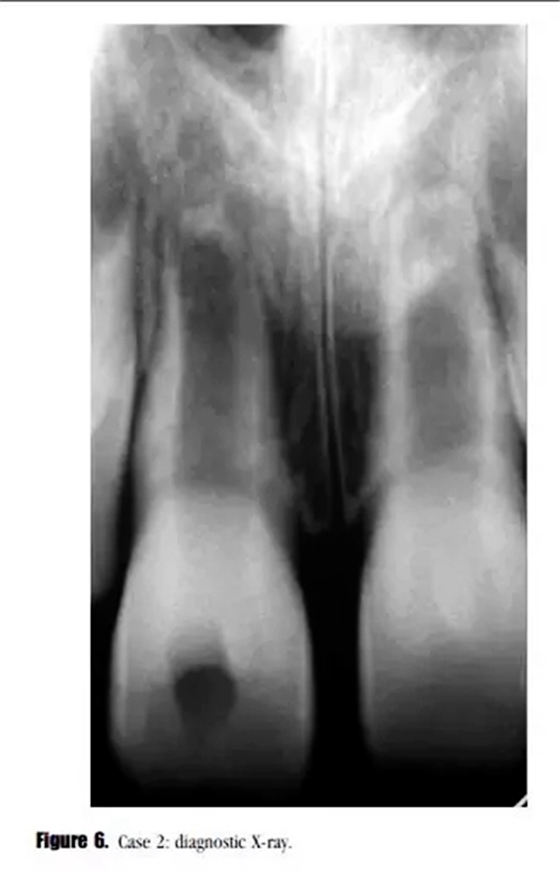

主訴:右上頜恒切牙區(qū)口腔前庭區(qū)腫脹。(圖6)。

??茩z查:牙齒輕微松動,可見開髓孔。叩診輕微不適,牙周探診深度在正常范圍內(nèi)。黏膜上可見一竇道。

輔助檢查:診斷X線示,牙根發(fā)育處于第4階段,未見明顯的根尖周透射影像,雙側(cè)中切牙根尖區(qū)可見阻射影像。21牙髓電活力測試結(jié)果正常。11診斷為:急性根尖周炎。

牙科病史:1天前于牙科急診部開髓。牙科病史還涉及患者從自行車上跌落后牙科創(chuàng)傷史。據(jù)家長描述,當時患牙松動程度更為明顯,牙齒周圍都是血,當時被診斷為牙齒不全脫位。但是沒有進一步進行治療。與患者家長溝通后,行牙髓血管再生治療。

采用與之前所述一致的方法對患牙進行治療,患者癥狀消失。在初次就診之后的3個月后,我們開始了第二次治療。術后X線顯示,牙根進一步發(fā)育,沒有牙根根管壁的沉積,MTA塌陷進入到血凝塊中。(圖7)